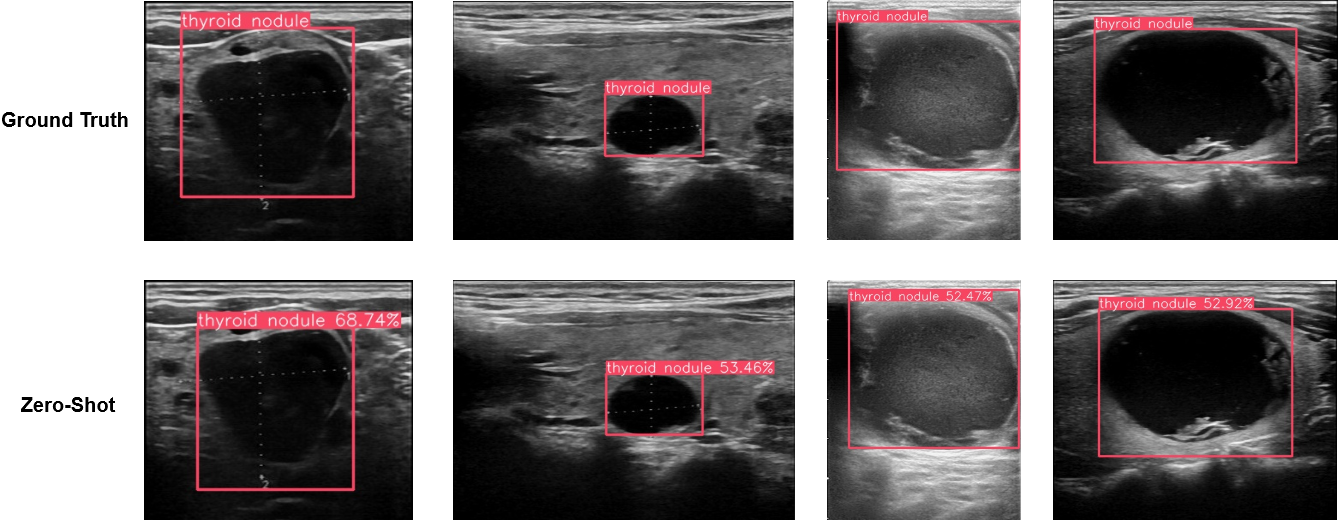

In this section, we provide some visualized examples to illustrate how attribute injection in prompts could affect the object detection for novel objects. In Figure 8, as we include more expressive attributes to the prompts, the predicted bbox can locate the target objects more accurately and confidently.

As demonstrated in Figure 9, we have shown several images and the predicted bounding boxes under the zero-shot setting on the TN3K dataset. As mentioned before, we directly use the class label as the text prompts for the radiology data, and, in this case, we simply use the ‘thryoid nodule’ to prompt the pre-trained VLM. As one can see, since the word ‘nodule” in the prompt has the language meaning of “small rounded or oval object…” in some context, the predicted bounding box in the zero-shot examples mostly aligned with the salient circle areas in the images. So, these examples prove our presumption that the unseen concept in radiology is too far different from the general image domain, and we need to provide extra visual examples to fine-tune the VLMs.